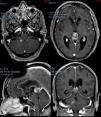

Presentamos el caso de una paciente de 72 años de edad sin antecedentes de interés que consultó en urgencias por un cuadro de 2 semanas de evolución de alteración de la marcha, cefalea y vómitos. El TAC craneal reveló la presencia de hidrocefalia obstructiva secundaria a una lesión pineal con impronta en el tercer ventrículo. La resonancia magnética mostró, además de la lesión ya referida, otra más pequeña situada en el foramen de Lushcka derecho. Se llevó a cabo una ventriculostomía endoscópica del suelo del tercer ventrículo y la biopsia endoscópica de la lesión, cuyo resultado fue de metástasis compatible con carcinoma de pulmón. Se realizó un TAC toracoabdominopélvico que mostró una masa pulmonar compatible con el carcinoma primario. Se decidió tratamiento sistémico de la enfermedad. La paciente falleció 2 meses tras el diagnóstico.

A 72-year-old female with no relevant medical history consulted in the emergency room for a two-week history of headache, vomiting and gait disturbance. Head CT scan revealed obstructive hydrocephalus secondary to a pineal mass with compression of the third ventricle. Magnetic Resonance showed another mass located in the right Lushcka foramen. Endoscopic third-ventriculostomy and biopsy of pineal mass were performed. Pathological analysis was consistent with metastasis of carcinoma. Full-body CT scan showed a lung mass related to primary carcinoma. The patient received systemic treatment for metastatic lung cancer. She died two months after diagnosis.